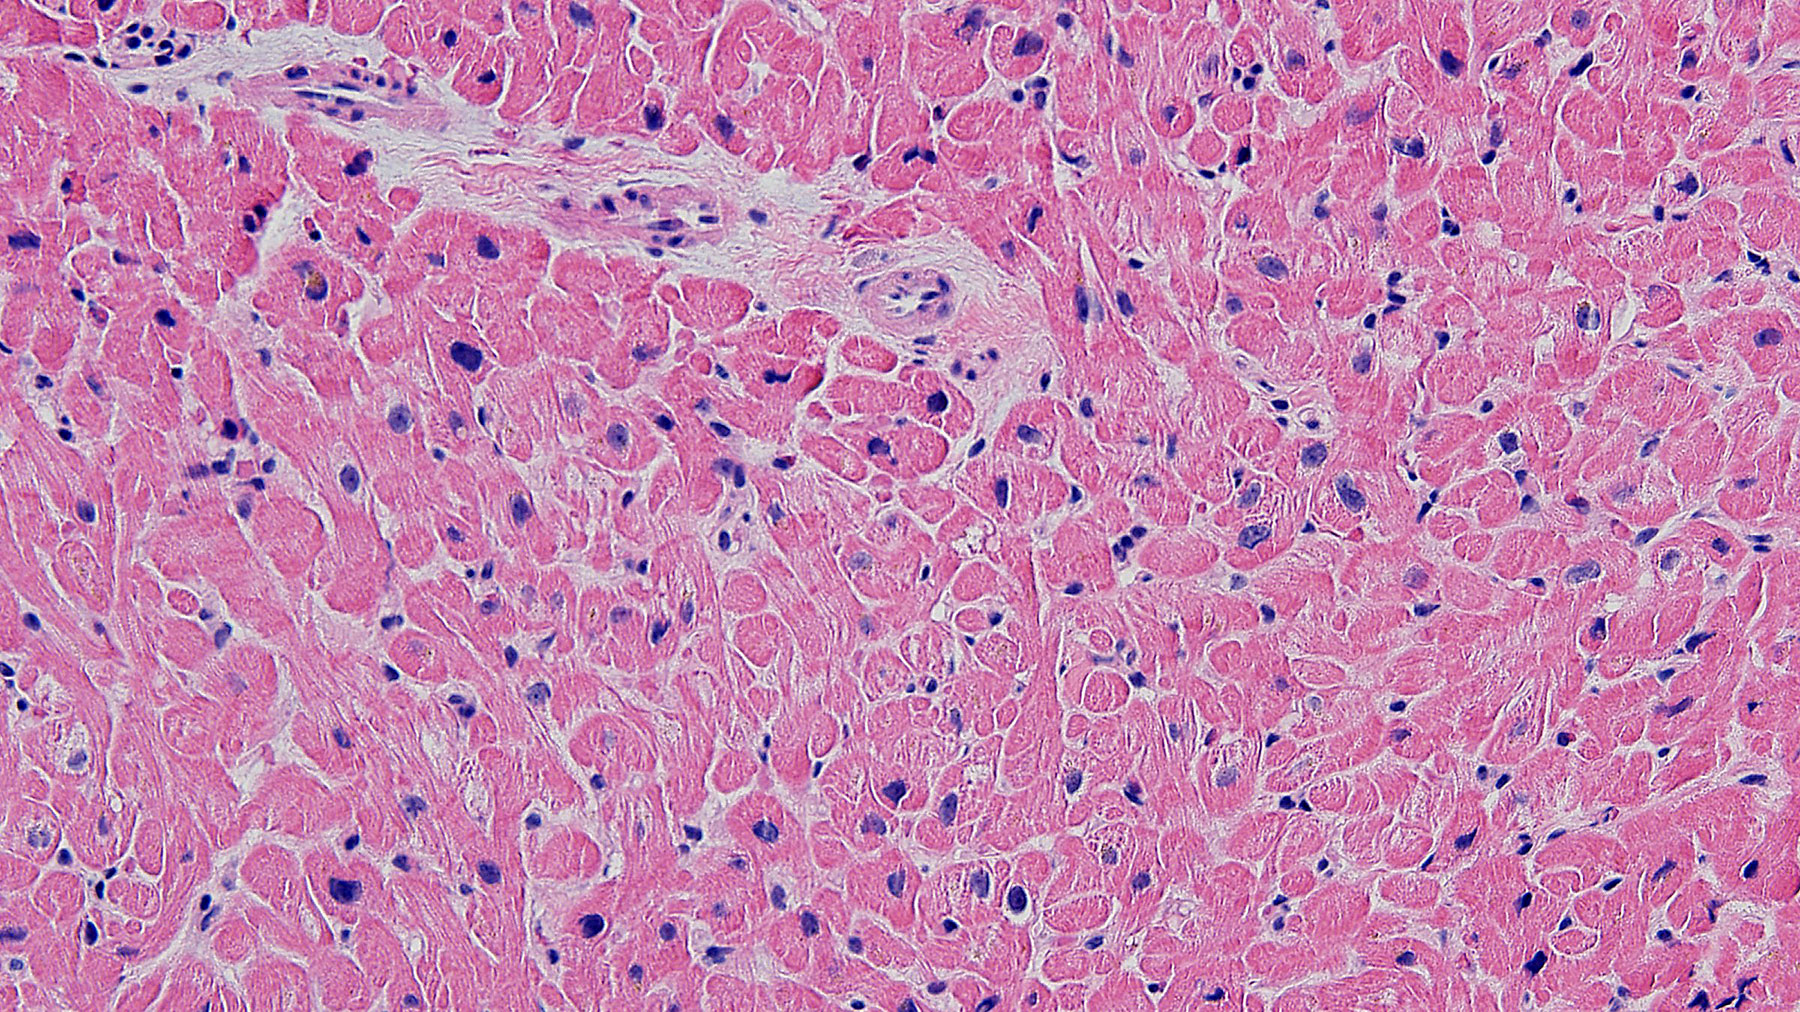

Figure A. Allograft myocardium with no evidence

of cellular or antibody allograft rejection